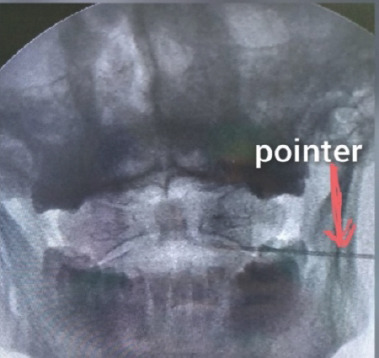

Patient positioning for atlantoaxial joint injection with bilateral spinal needles visible on AP and lateral fluoroscopic views.

Fluoroscopic Target Acquisition:

• On AP imaging, target the junction of the medial two-thirds and lateral one-third of the joint (either C1 inferior articular process or C2 superior articular process)

• The C1-2 joint is noncongruent (C2 articular pillar is convex superiorly), so it is seen crisply over an arc of fluoroscopic rotation

• To find the posterior joint: decline the fluoroscope until the lucent joint space is lost, then rotate cranially until joint lucency and crisp cortical margins are first acquired — this images the posterior aspect the needle must enter

• True AP is verified by centering the dens within the ring of C1 and ensuring C2 pedicles are equidistant from the spinous process